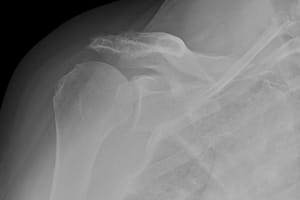

BEFORE:

This is an x-ray before surgery demonstrating shoulder arthritis associated with an irreparable rotator cuff tear.